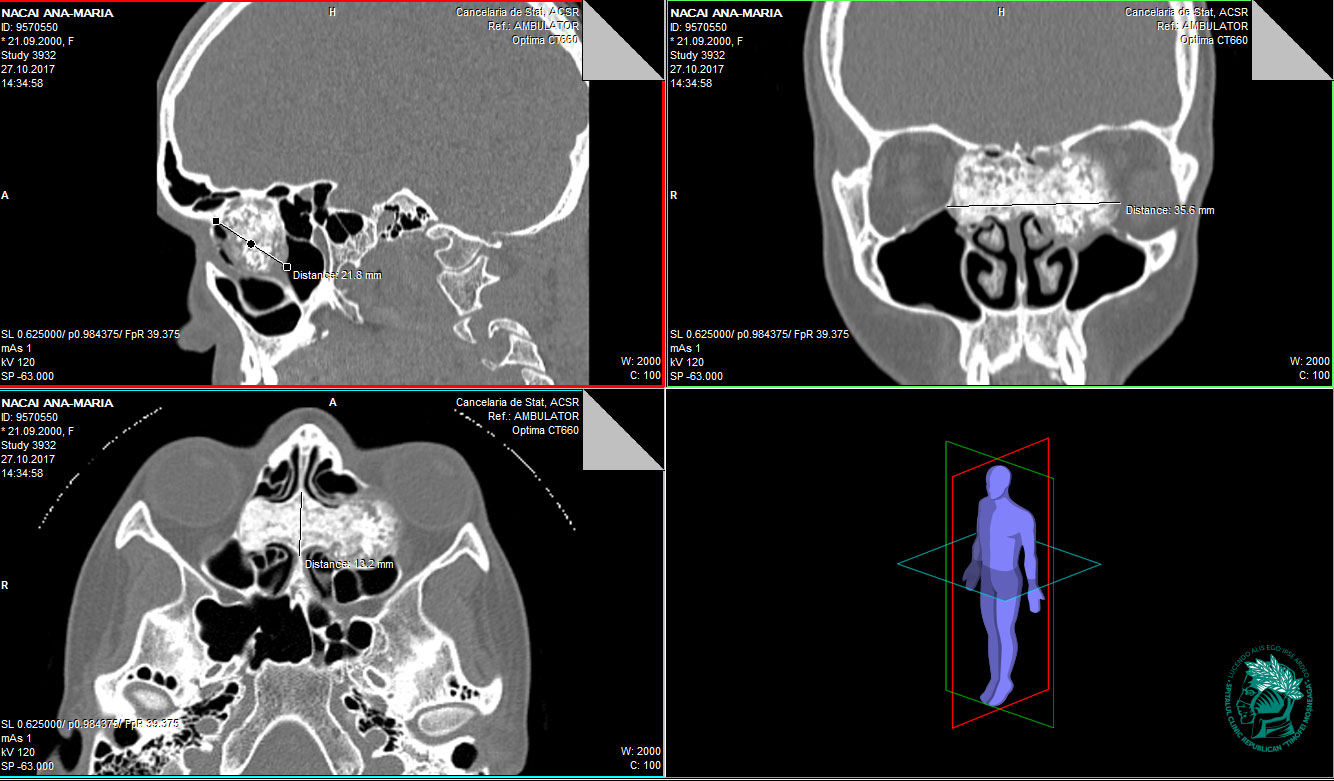

Această intervenție este o premieră la nivel național. Chirurgul menționează, că intervenția a fost una destul de complicată din cauza localizării tumorii,fixată superior de baza craniului, iar lateral cu invadarea orbitelor și compresia globului ocular, vascularizată de arterele etmoidale anterioare și posterioare care vin din bazinul arterei carotide externe și interne. Dimensiunea tumorii a fost 3,5 cm în lățime și 2 cm în adâncime, fiind cea mai mare dimensiune a unui osteom întîlnit în practica Dr. Bajureanu. Intervenția a durat 5 ore 30 min, cu prezența unei hemoragii moderate controlate. Pentru a evita traumatizarea țesuturilor, tumoarea a fost înlăturată treptat, milimetru cu milimetru, cu ajutorul frezelor demantate. Conform rezultatului histologic, s-a confirmat prezența unei tumori benigne, osteom de tip mixt.